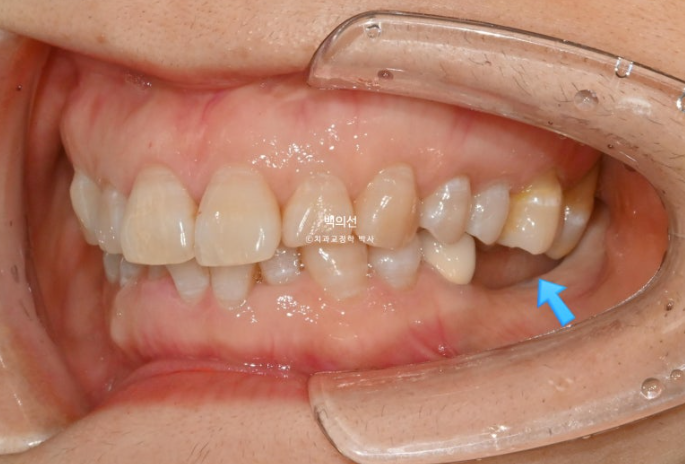

다른 문제가 하나 더 있습니다. 파란 화살표 치아는 신경치료 된 치아인데 뿌리끝에 염증이 있습니다.

이 치아 역시 타병원에서 쓸때까지 쓰다가 문제 생기면 발치 후 임플란트 하는 걸로 알고 계셨습니다.

인비절라인이 이와같이 치근단 염증이 있거나 잇몸이 약해 교정력이 가해지지 않아야할 치아들이 있는 경우 큰 장점이 있습니다.

치료의 처음부터 끝까지 치아이동이 없게끔 치료계획을 세우면, 약간 치아에 무리가 가지 않게 나머지 타겟치아들만 움직이면서 교정이 가능합니다.